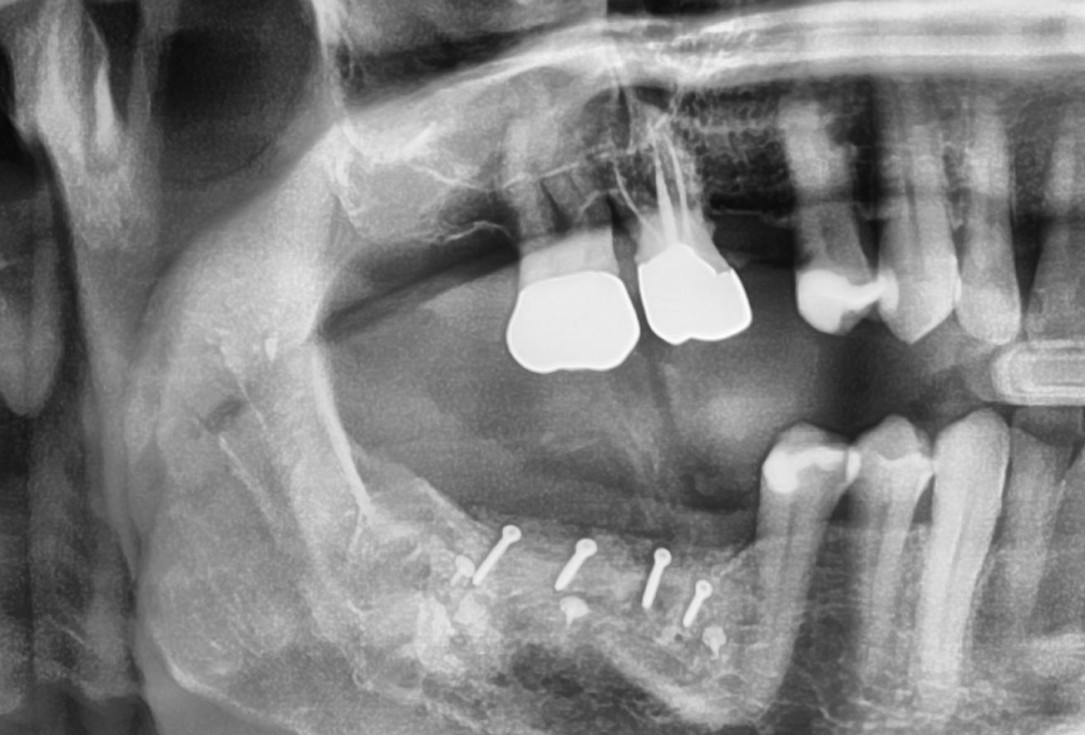

11/28 - X-ray scan after augmentationThree-dimensional augmentation with maxgraft® cortico - Dr. R. Würdinger